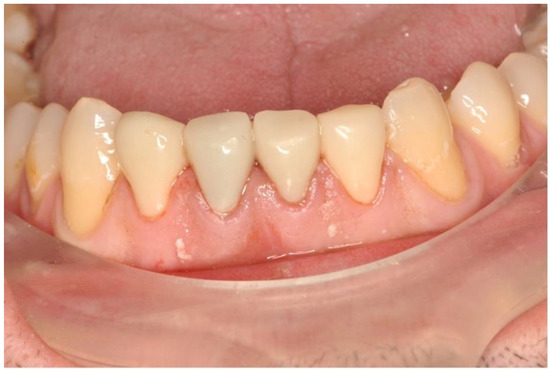

2. Case Description

3. Clinical Procedure and Outcome